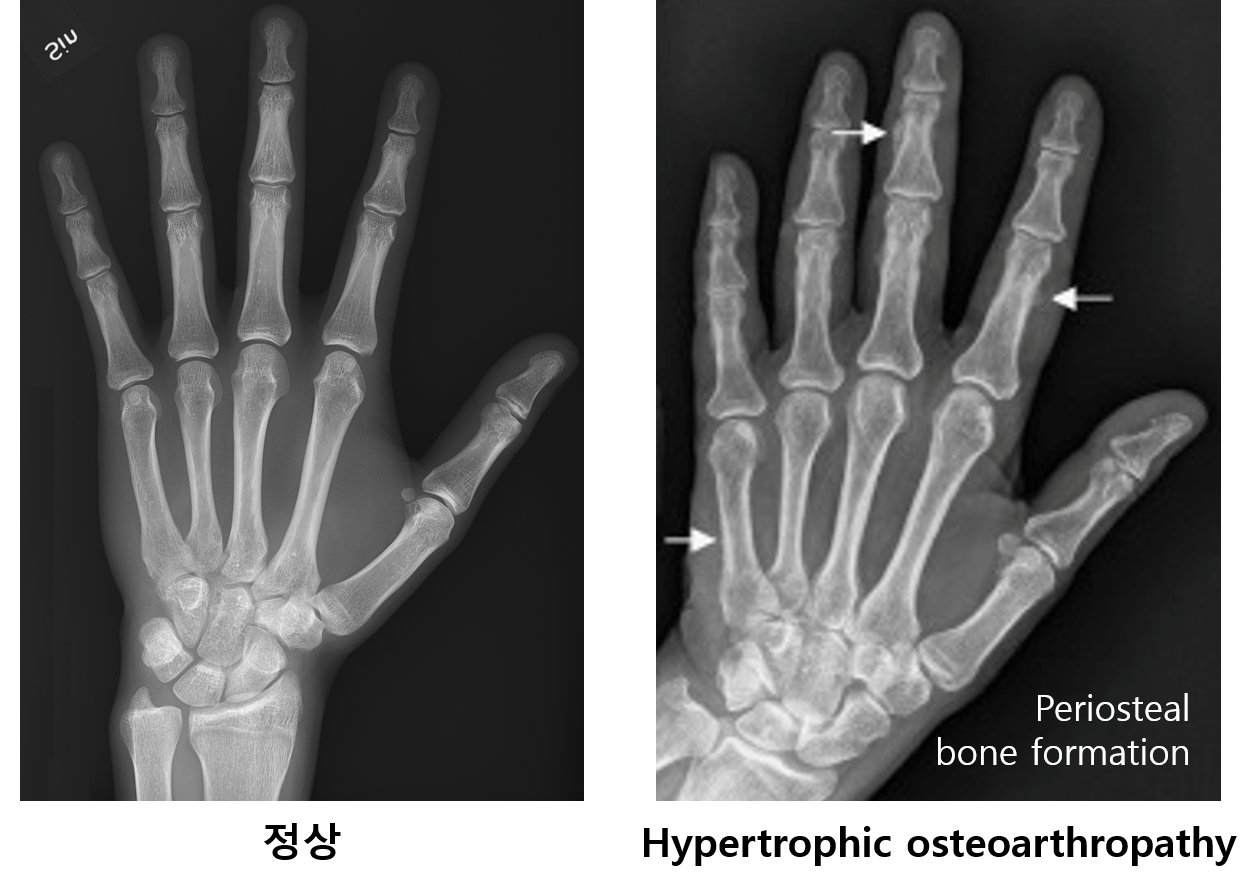

6. 비대성 골관절증(hypertrophic osteoarthropathy, HOA)

1) 개요

(1) 곤봉지(finger clubbing)와 골막 골생성(periosteal bone formation)을 나타내는 근골격계 질환

(2) 분류

① 일차성: 상염색체 우성 유전 → 사춘기에 증상 시작 → 성인기에 증상 소실

② 이차성: 다양한 질환들과 연관 (악성 종양, 선천성 청색증성 심질환, 만성 호흡기 질환, 염증성 장질환 등)

2) 임상양상

(1) 곤봉지: Nail bed, distal phalanx의 volar pad가 두꺼워져 곤봉 모양으로 변형됨

(2) 관절통: Periosteal bone formation으로 인해 발생 (뼈 가장자리의 골막에 붙어 새로이 뼈가 자라남)

3) 치료: 원인 질환 치료